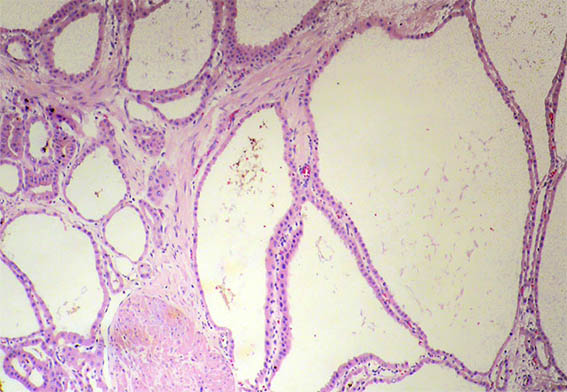

Figure 2. H&E, X40.